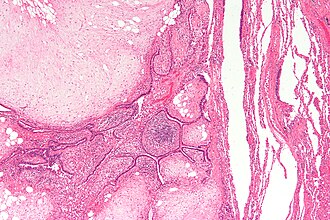

Template:Px Pulmonary hamartoma. H&E stain. | |

| LM | benign cartilage, adipocytes and respiratory epithelium; lesion without significant nuclear atypia |

Features:

- Cartilage - key feature.

- Single cells in lacunae surrounded by abundant matrix.

- Paucicellular vis-a-vis malignant lesions.

- Fat (adipocytes) - key feature.

- Respiratory epithelium (columnar epithelium with cilia).

- No nuclear atypia.